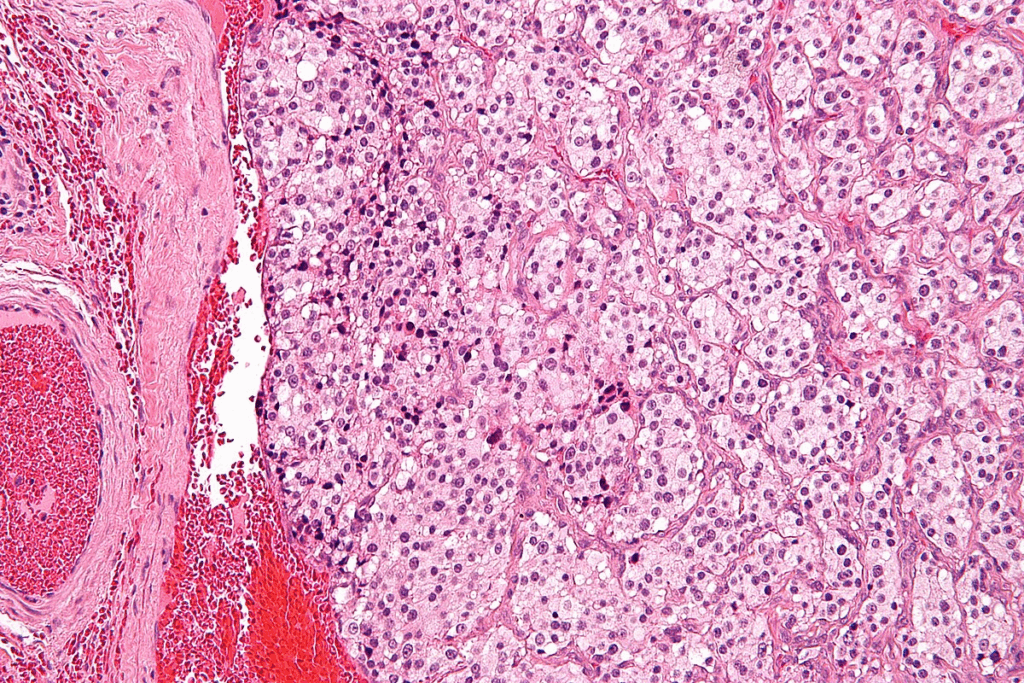

Bladder cancer is a type of cancer that begins in the bladder. The bladder is a hollow organ in the pelvis that stores urine. Most bladder cancers start in the urothelial cells that line the inside of the bladder.

Urothelial carcinoma, also known as transitional cell carcinoma, is the most common type. It accounts for about 90% of all bladder cancer cases.